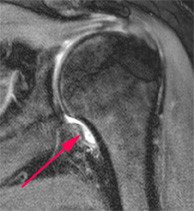

MRI Frozen Shoulder

Dieses MRI-Bild zeigt eine deutliche Verringerung des Volumens, in dem sich das Kontrastmittel verteilen kann. Die Kapsel ist geschrumpft und schränkt dadurch die Beweglichkeit des Gelenkes stark ein